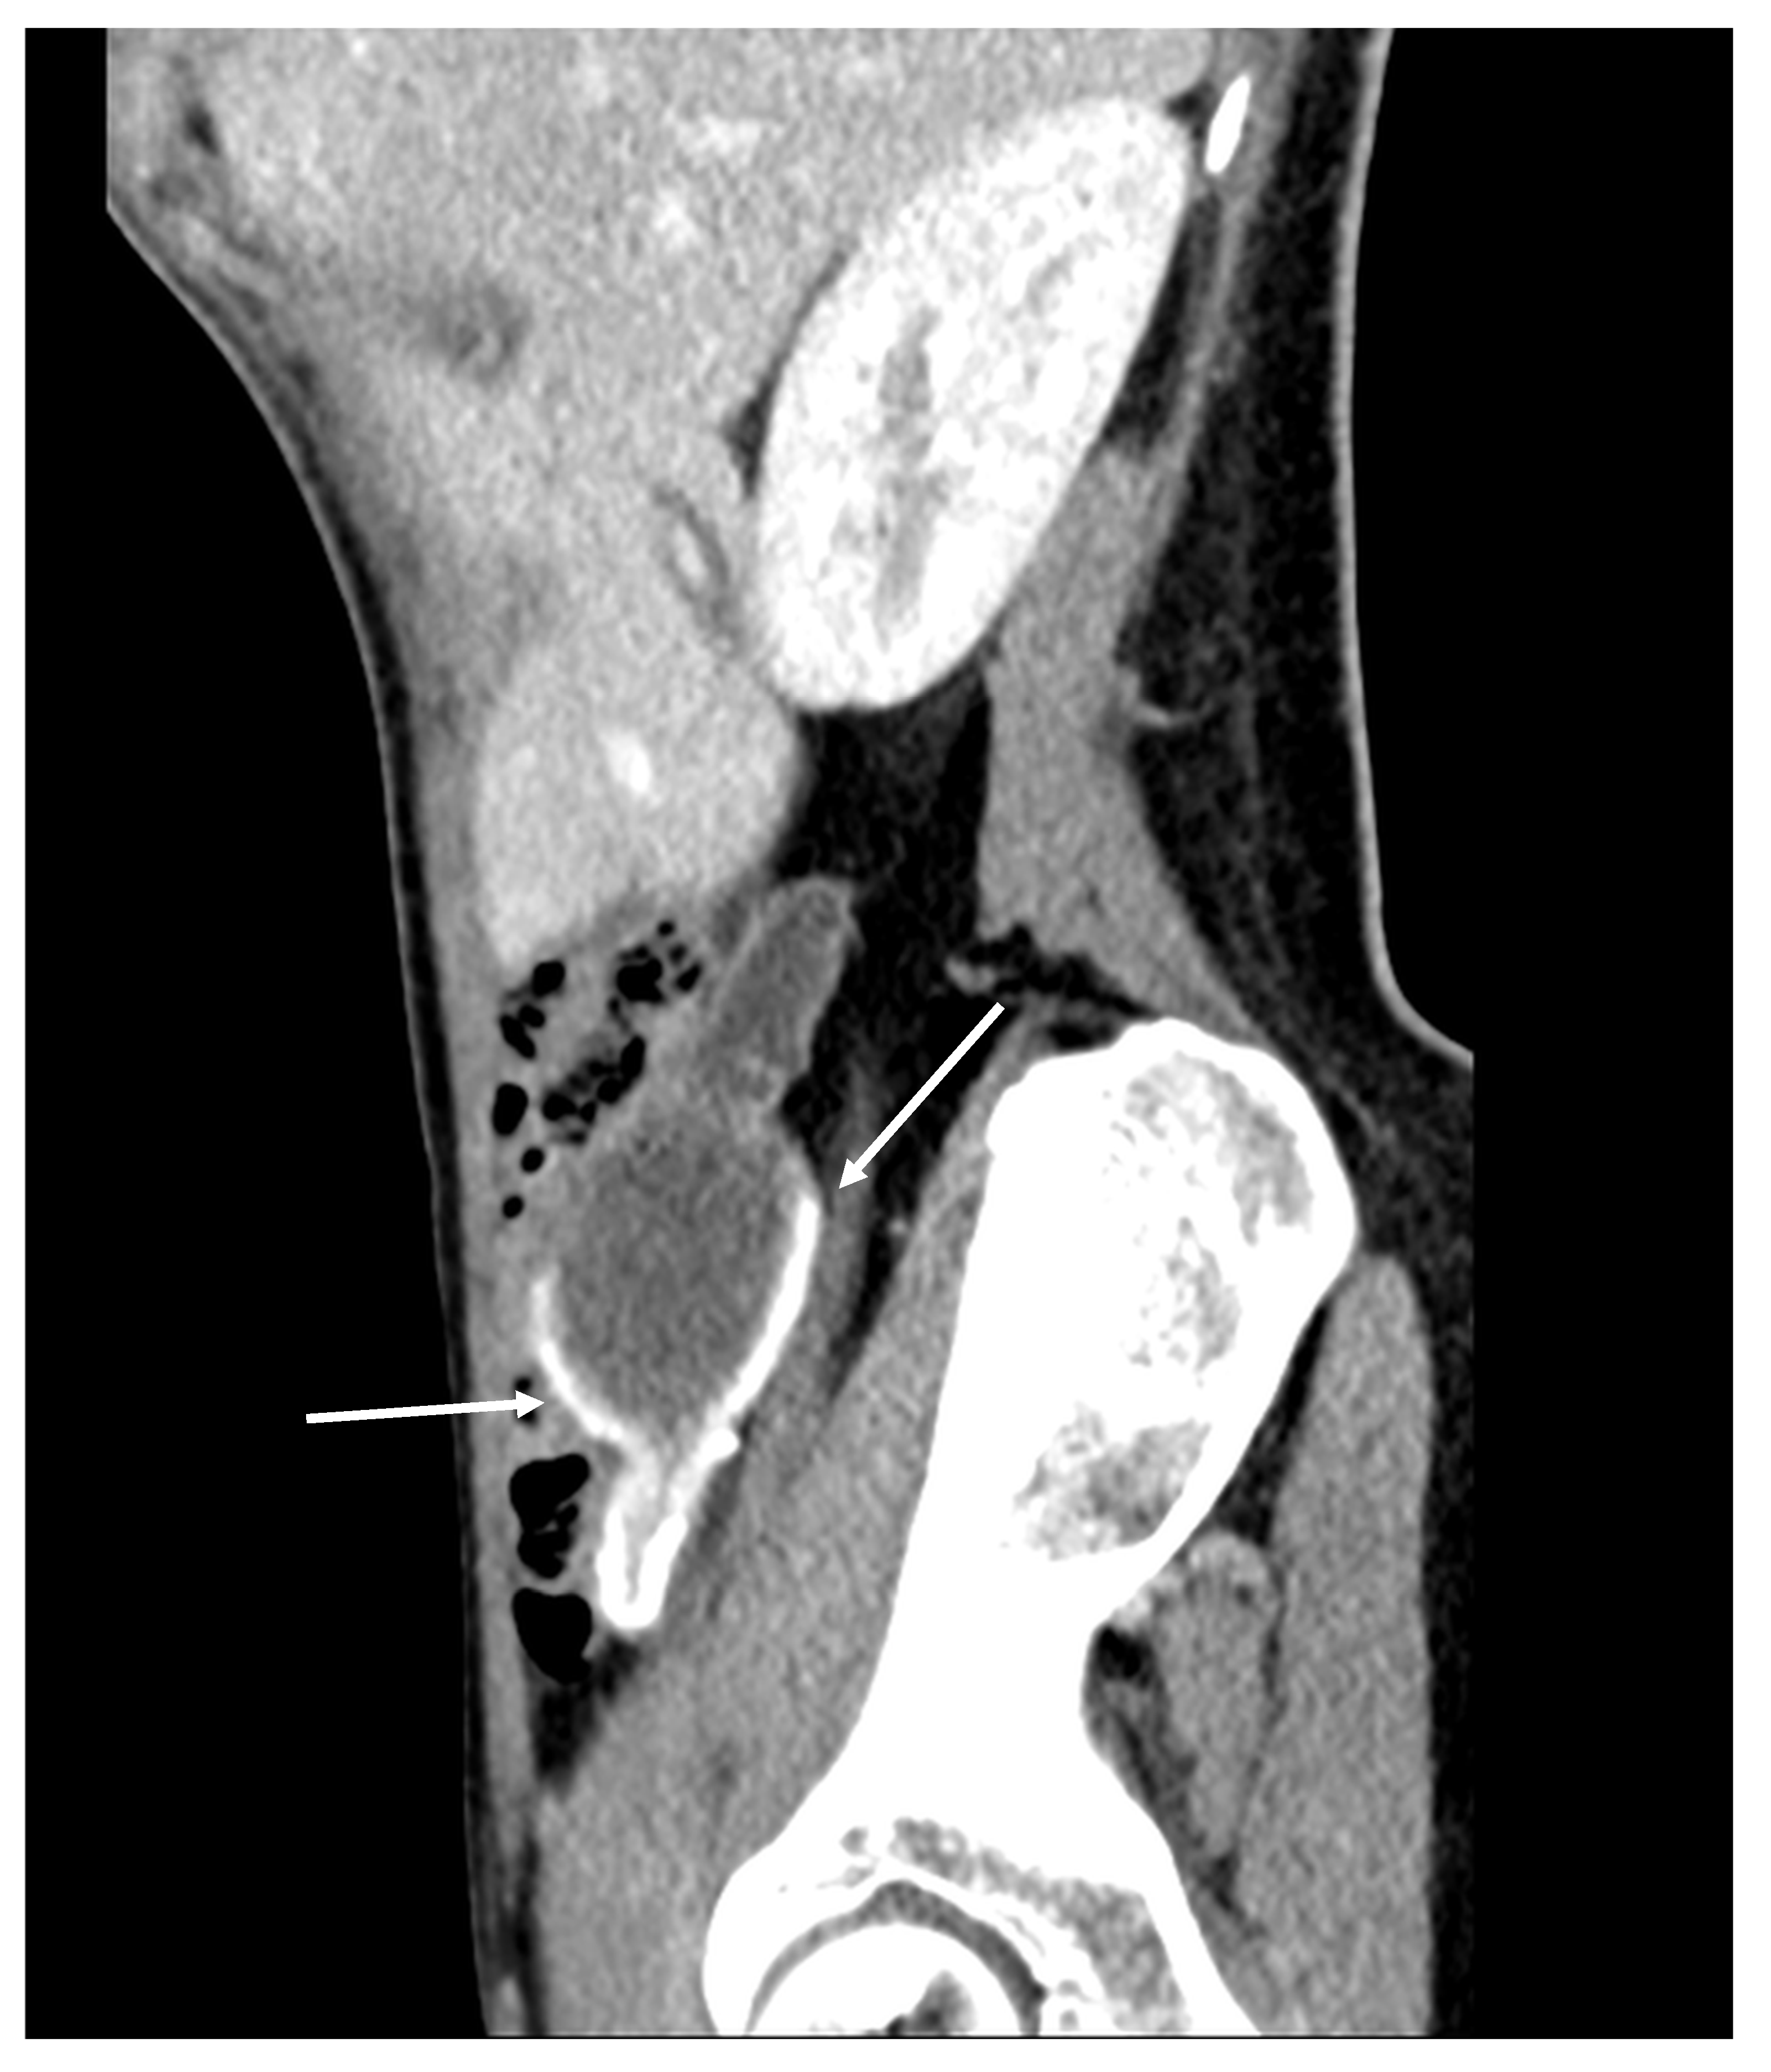

Figure 2. Mucocele of the appendix with calcification in the mucocele’s wall (arrows) (CT, venous phase, sagittal plane). Cystic dilatation of the appendix and calcification in the appendiceal wall. This is a typical sign for a mucocele, and it is present in 50% of patients [9].